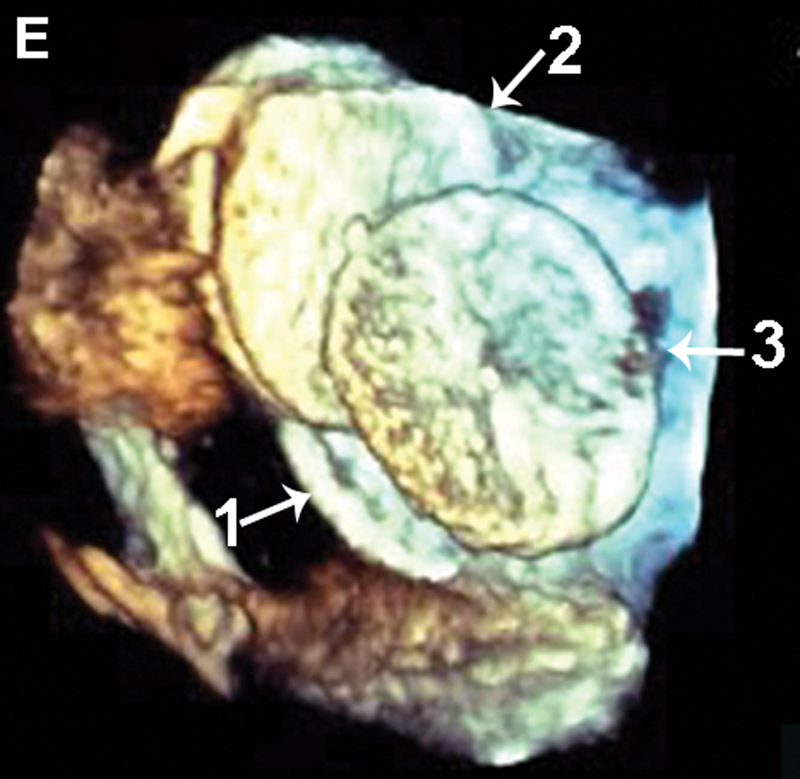

فحوصات تشخيصية لبعض امراض القلب والشرايين التاجية